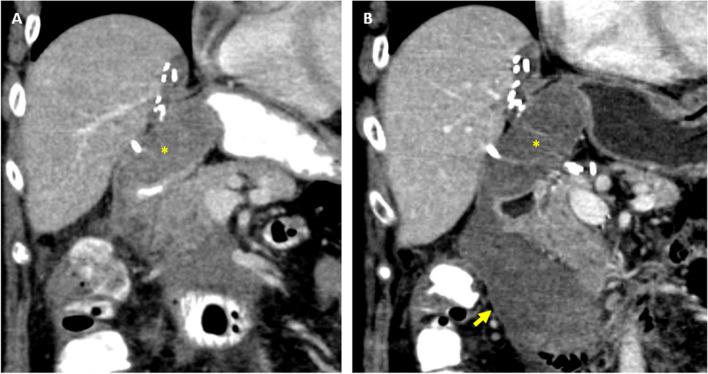

Case presentation: A patient presented with an enlarging hematoma due to bleeding at the gastroduodenal artery HAIP catheter insertion site. Emergent angiography revealed concomitant common hepatic artery occlusion and retrograde perfusion of the GDA via tortuous, diminutive hepatic collaterals which precluded standard antegrade approach. Collateral inflow from the dorsal pancreatic artery was utilized to opacify the right hepatic artery. The segment 5 hepatic artery was percutaneously accessed under fluoroscopic guidance, and microcoils were deployed both proximal and distal to origin of the gastroduodenal artery. The patient remained stable throughout the postoperative period and was discharged after an otherwise uneventful admission. Follow-up computed tomography demonstrated resolution of the hematoma and no bleeding or biliary complication from transhepatic access.